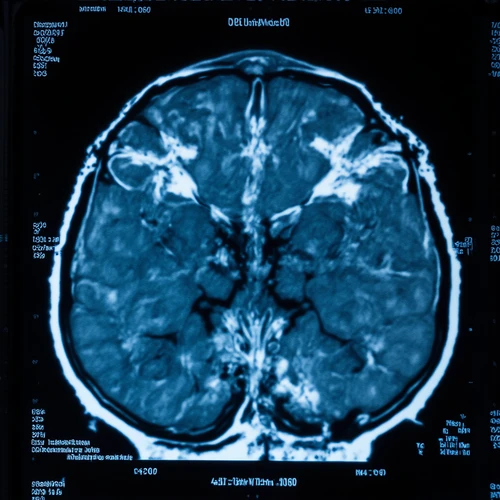

Advanced MRI Detects Early Frontotemporal Dementia

A multinational investigation spearheaded by investigators at Karolinska Institutet shows that subtle neuronal alterations can be identified early in hereditary frontotemporal dementia (FTD) through cutting‑edge magnetic‑resonance imaging. The findings appear in Molecular Psychiatry.

Frontotemporal dementia is a neurodegenerative condition most common before 65 years of age and notoriously difficult to diagnose early. Initial symptoms are often behavioural and can mimic primary psychiatric illness, while later manifestations resemble Alzheimer’s or Parkinson’s disease. Roughly one third of cases carry a known genetic mutation, making mutation carriers a valuable cohort for research.

The research team, in partnership with a global consortium, examined brain microstructure in over 700 participants, including both mutation carriers and control subjects.

They employed a novel diffusion‑weighted MRI technique that gauges how water molecules move within gray‑matter tissue – greater spread reflects microstructural damage before overt cortical thinning or brain atrophy becomes apparent.

Compared to the standard method of measuring cortical thickness, the new approach proved more sensitive. In carriers of the C9orf72 mutation, detectable change occurred before any clinical sign emerged; MAPT mutation carriers showed alterations at mild symptomatic stages, while GRN mutation carriers developed changes only in more advanced phases.